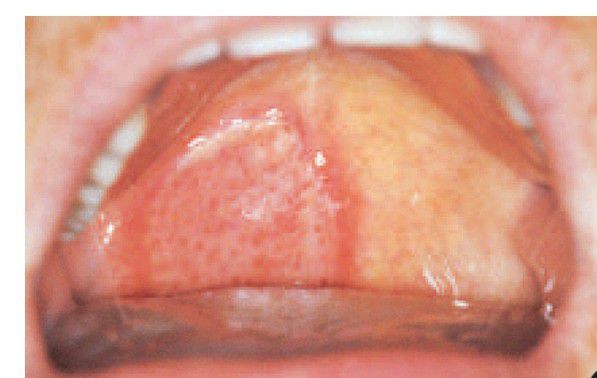

Localised oral purpura

. A ruptured blood blister has formed a large ulcer on the soft palate.